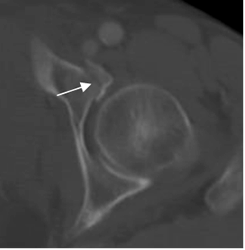

Fig 59. Fragmentos libres.

A y B: TAC axial. Fracturas del acetábulo no mostradas, con fragmentos libre intra-articulares.